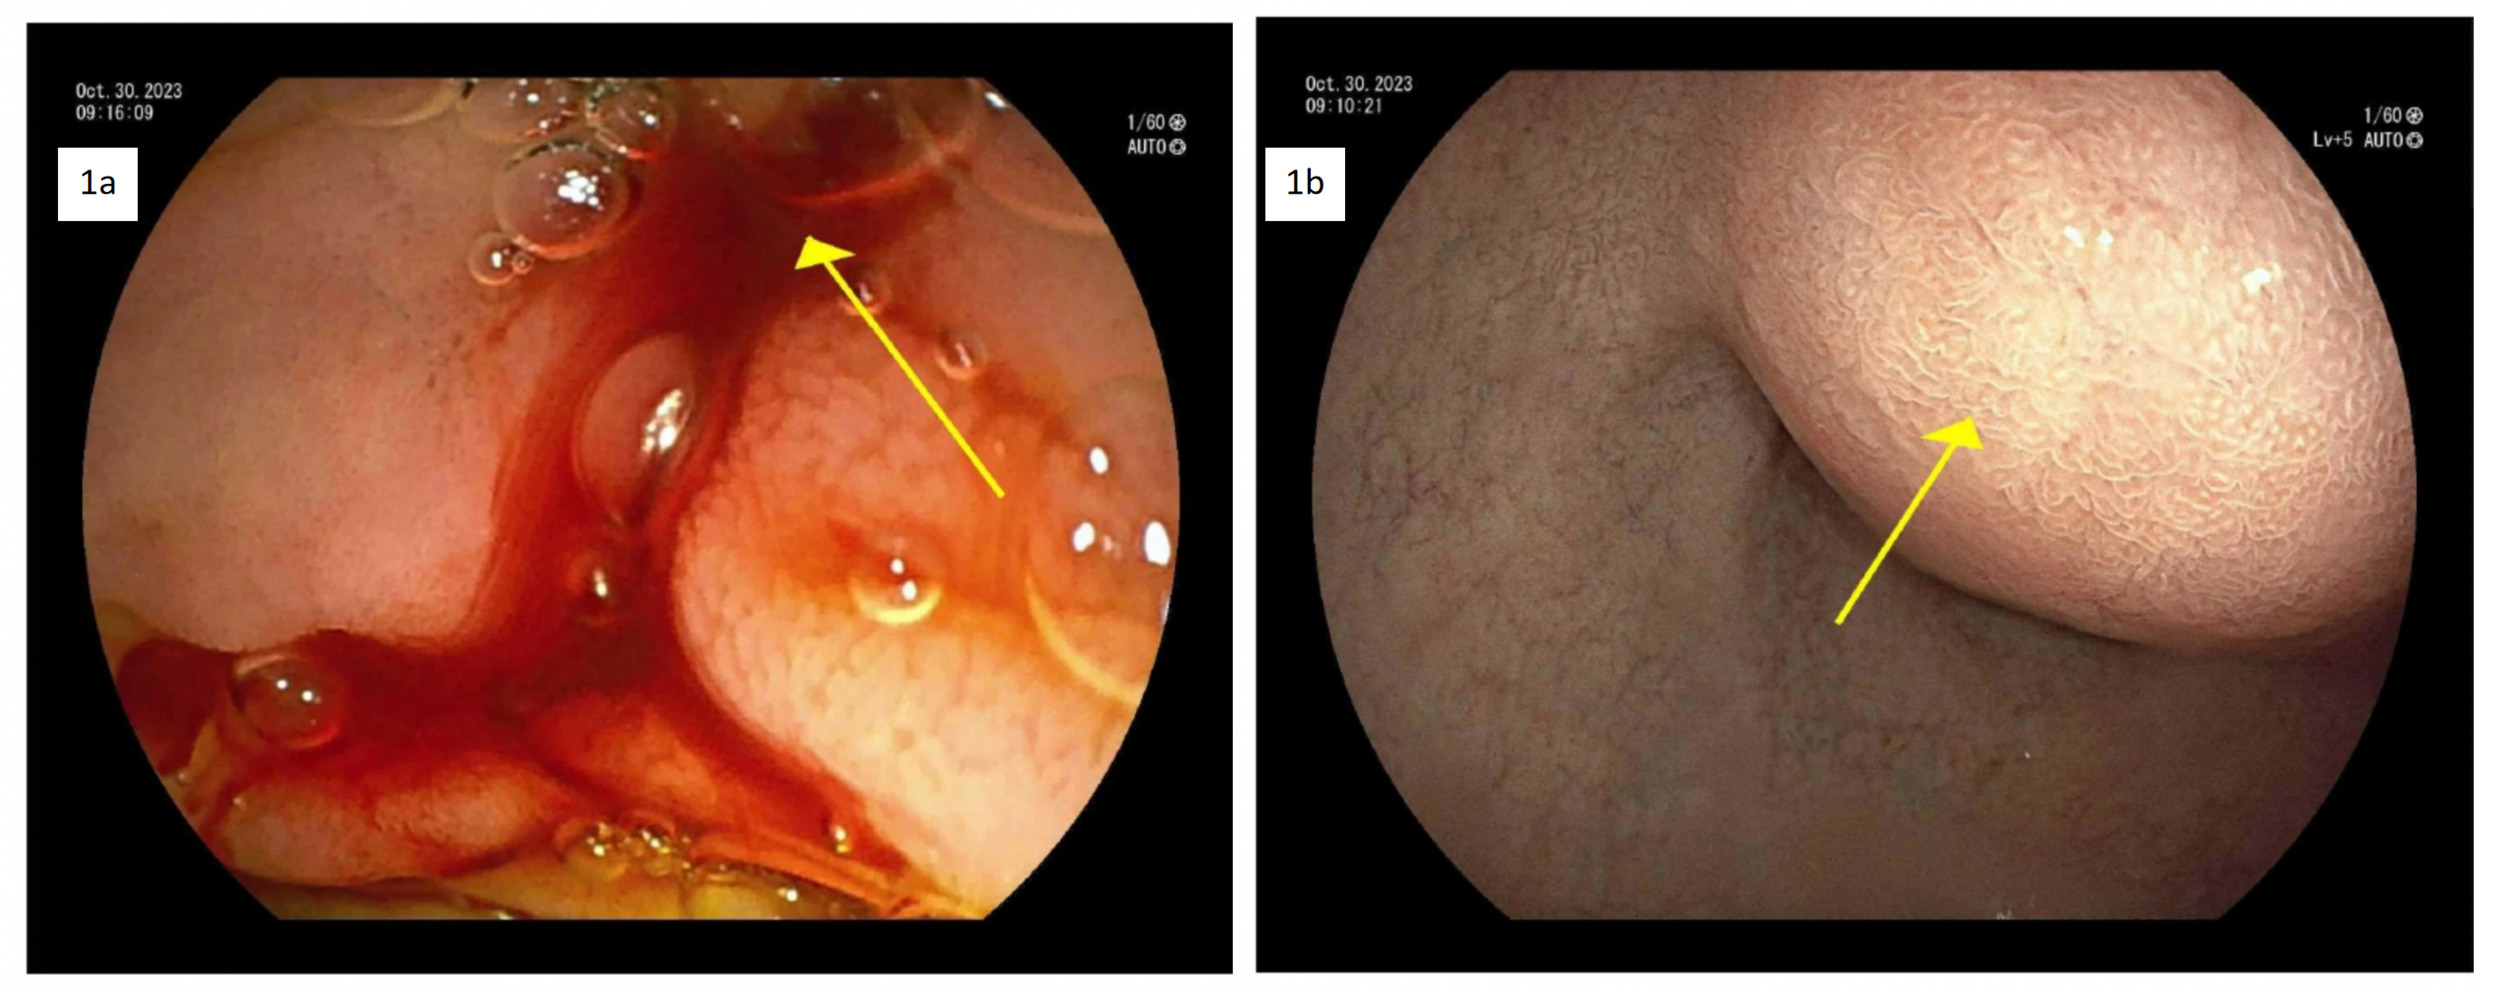

On day 1, the immediate management required 2 units (560 mL) of packed red blood cell transfusion. Further evaluation with a contrast Computed Tomography (CT) scan of the abdomen to identify the source of bleeding revealed a heterogeneous lesion along the pancreatic head and uncinate process, measuring approximately 4.1 x 3.7 cm. There were multiple enhancing foci along the mass-like structures, the largest measuring 1.6 x 0.9 cm. Similar lesions were noted in the pancreatic head and tail, suggesting sequelae of chronic pancreatitis. Gastroenterology was consulted. After stabilization, on day 2, the patient underwent upper gastrointestinal endoscopy (UGIE) with endoscopic ultrasound (EUS). The EUS showed findings suggestive of chronic pancreatitis with multiple cysts, and the UGIE showed active bleeding from the ampulla of Vater [Figure 1a] and subepithelial prominence of the duodenal bulb [Figure 1b], likely from the pancreatic pseudoaneurysm.